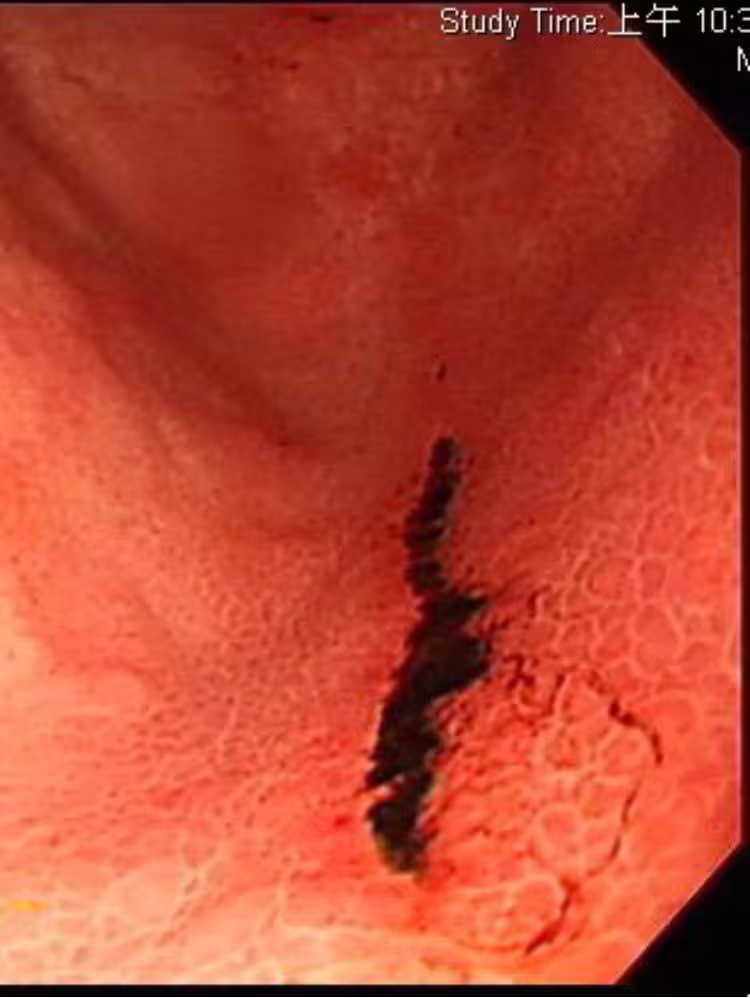

經過醫師的精密檢查,發現這名40多歲男子的胃竟有多達5處的潰爛傷口,某些嚴重的部位甚至有出血情況,可見病情嚴重。 但離奇的是,平時他並沒有不良習慣,用餐也相對清淡、規律,更沒有喝咖啡、茶、果汁等飲品,甚至連零食都沒有吃,照理來說並不會出現那麼可怕的潰瘍傷口。